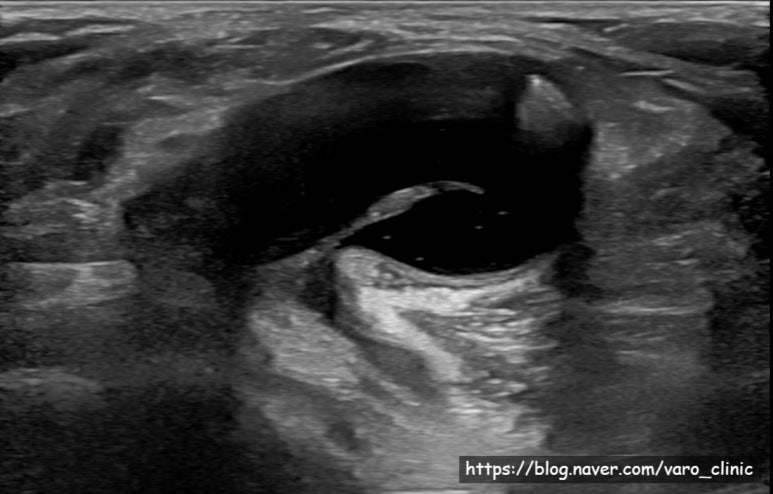

※ 개인정보활용동의를 얻은 환자분의 영상기록 사본입니다. 무단 복사를 금지합니다. ​무릎 뒤 오금이 유난히 튀어나온 것 같다며 강서구에서 내원한 환자분입니다. 이 뿐만 아니라 걸을 때마다 무릎이 시큰시큰하다고 하시는데요.​초음파 영상이 담긴 CD를 복사해 오셨는데, 무릎 뒷쪽에 커다란 종양이 보입니다. 이게 도대체 뭘까요?​바로 "베이커 낭종"입니다.​ 베